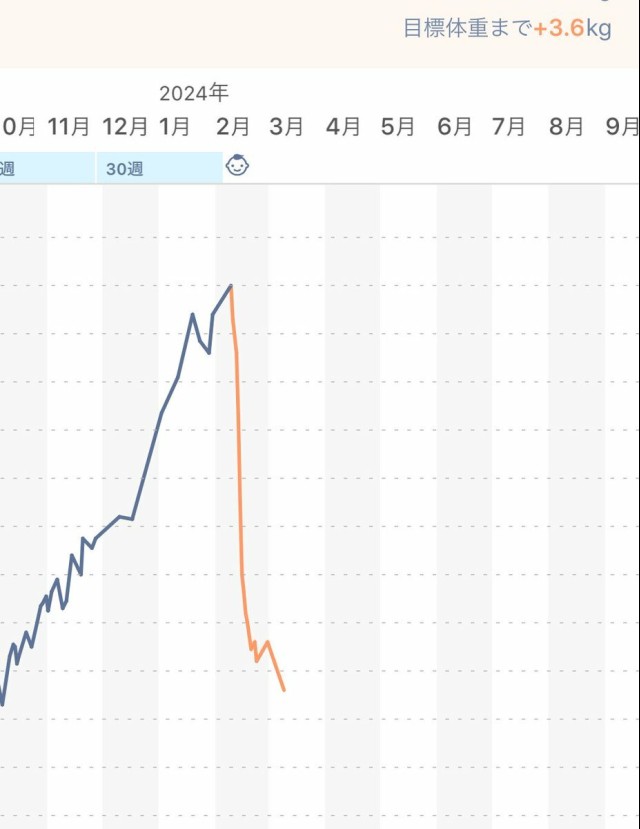

体重管理 久しぶりに体重測ったらまた少し落ちてた 無理のない範囲でがんばろ

体重管理 ?妊娠前体重より5%以上体重減だと入院治療対象になるようです?水分栄養取れていないようなら、みおさん含めお腹の子の為に、早めに受診された方が良いと思います?

体重管理 さすがに鈍化してはきたけど、それでも落ちてるぞお? 妊娠前の体重まであと10kgか